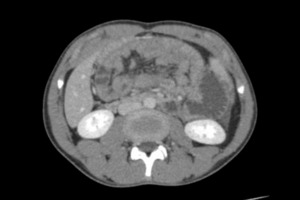

On examination, he was ill-looking and dehydrated, with a pulse rate of 110 beats per minute and a blood pressure of 80/50 mmHg. He was febrile and running the temperature of 39 degrees Celsius. Abdominal examination revealed a distended and diffusely tender abdomen with sluggish bowel sounds. Laboratory blood investigations were all normal. An erect X-ray of the abdomen showed few dilated small bowel loops predominantly occupying the left hypochondrial region. A computed tomography scan of the abdomen demonstrated sac-like clustered small bowel loops noted in the left upper quadrant, in the anterior pararenal space, consistent with the diagnosis of left paraduodenal hernia.

The diagnosis of PDHs is the most challenging aspect of management. This is because of the non-specific presentation of PDH. Presenting symptoms can range from diffuse abdominal pain that is frequently eased by positional modifications to acute intestinal obstruction, which is the most common presentation.8 A contrast CT scan of the abdomen plays a crucial role (sensitivity: 95-100%, specificity: 95%) and, in most cases, confirms the diagnosis.9 This is in addition to a thorough medical history, a clinical examination of the patient, an abdominal X-ray, an abdominal ultrasound, and laboratory tests.9

The importance of CT in the early preoperative identification of PDH is justified by the significant death rate associated with these complications.10 The typical CT finding is a mass of dilated small intestinal loops arranged abnormally between the stomach and pancreas to the left of the Trietz ligament. The transverse colon, the duodenal flexure, and the posterior wall of the stomach are frequently displaced due to a mass effect. At the entry of the hernial sac, the mesenteric arteries supplying the herniated small bowel seem congested, engorged, and stretched.11,12